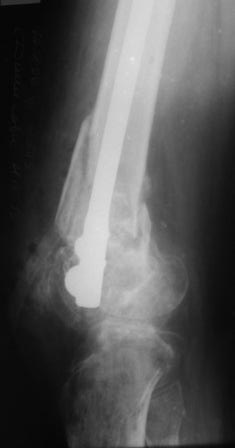

Уважаемые коллеги! Представляю на ваш суд ближйший результаты лечения.

На момент операции не было возможности запечатлеть увиденное, поэтому попытаюсь пересказать.

Первое что пришло в голову по аналогии очень похоже на асептический некроз головки бедра когда головку извлекают при эндопротезировании.Хрящ внутреннего мыщелка бедра был отслоен и изменен,сам мыщелок проминался под пальцем. От блокирования стяжкой отказались. Можно ли это расценить как асептический неркоз внутреннего мыщелка в результате первичной травмы?

Леонид Соломин писал о случае с пателлофеморальным синдесмозом(спасибо), но к сожалению сообщение пришло уже после операции.Прежде мы не встречались с подобным.Во время мобилизации после артролиза, отсечения интремедиуса попытались согнуть колено: хрящ надколенника остался на мыщелках бедра(!). В результате приняли решение удалить надколенник.

Раннее послеоперационное течение не очень спокойное- из раны было сукровичное отделяемое, но сейчас вроде идет на поправку(на фоне интенсивного лечения). В аттаче рентгенограммы.